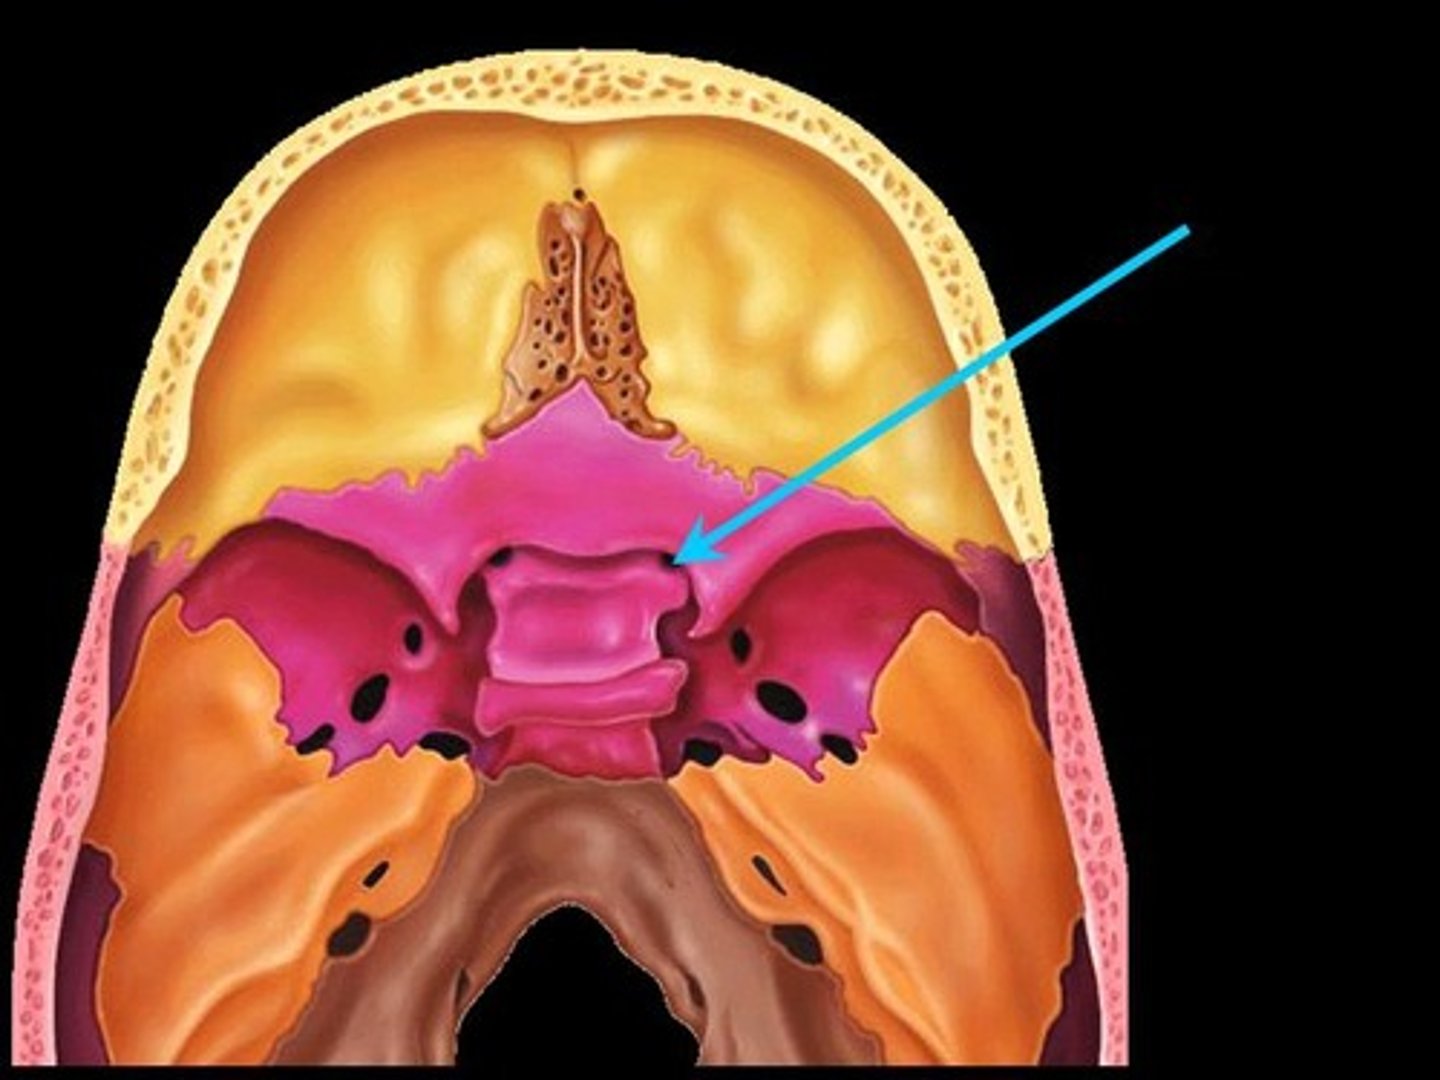

Third Ventricle

One of four connected fluid-filled cavities comprising the ventricular system within the human brain. The central cavity of the brain, lying between the thalamus and hypothalamus of the two cerebral hemispheres.

Choroid Plexus

A highly vascular portion of the lining of the ventricles that secretes cerebrospinal fluid.